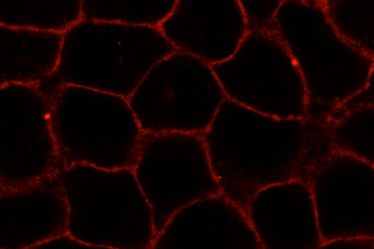

Dynamische Zellkontakte: CiM-Studie zur Verbindung von Endothelzellen und der Bildung von Blutgefäßen

Dynamische Zellkontakte: CiM-Studie zur Verbindung von Endothelzellen und der Bildung von Blutgefäßen